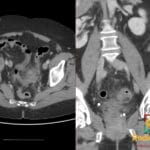

- Radiology Cases: Images with a to-the-point discussion highlighting the specific diagnostic criteria.

Latest Radiology Cases